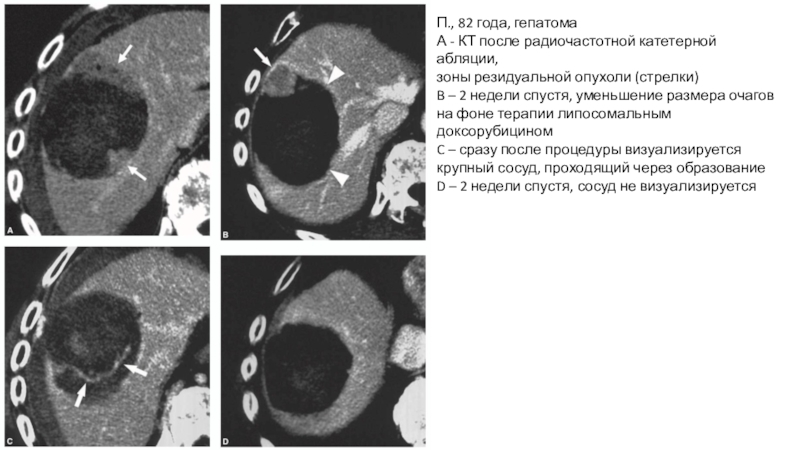

Слайд 18П., 82 года, гепатома

А - КТ после радиочастотной катетерной абляции,

зоны

резидуальной опухоли (стрелки)

B – 2 недели спустя, уменьшение размера очагов

на фоне терапии липосомальным доксорубицином

C – сразу после процедуры визуализируется крупный сосуд, проходящий через образование

D – 2 недели спустя, сосуд не визуализируется

П., 82 года, гепатомаА - КТ после радиочастотной катетерной абляции,зоны резидуальной опухоли (стрелки)B – 2 недели спустя,